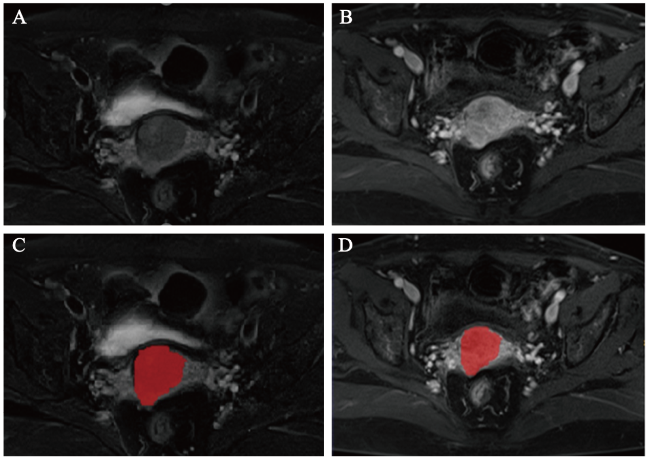

图2 训练集和验证集的LR、NB、SVM、KNN、RF和LightGBM的ROC曲线注:A为训练集的LR、NB、SVM、KNN、RF和LightGBM的ROC曲线;B为验证集的LR、NB、SVM、KNN、RF和LightGBM的ROC曲线。 |